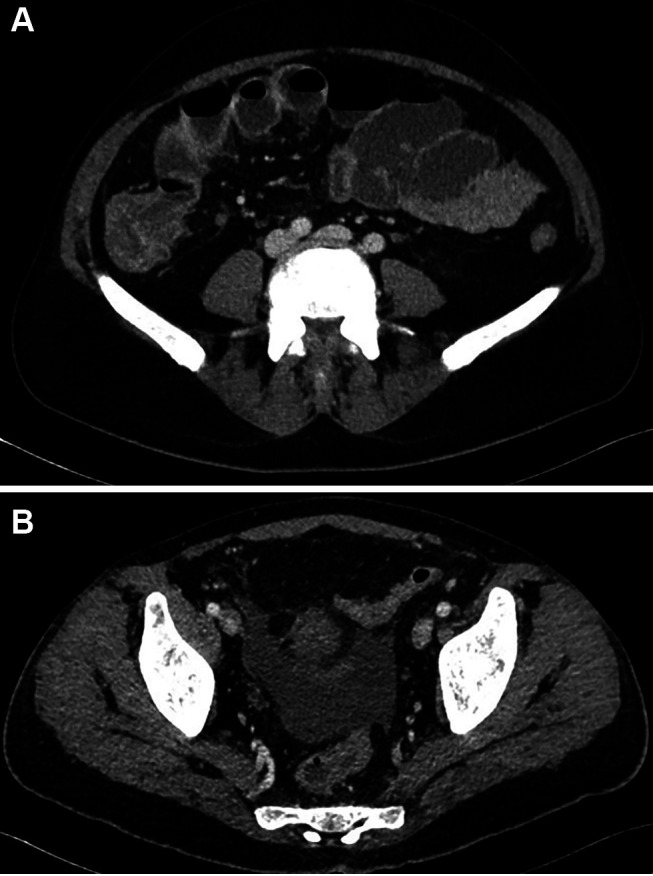

Case report: We report the case of a 44-year-old male with acute myeloid leukemia (AML) and intestinal Behçet's disease who developed severe NE during induction chemotherapy. Initial conservative management was guided by serial cross-sectional imaging, which revealed progressive bowel wall thickening, pneumatosis intestinalis, and signs of ileus. The clinical course was complicated by septic shock, multiorgan dysfunction, and later, acute gastrointestinal hemorrhage. Active arterial bleeding was identified via computed tomography angiography and successfully treated with interventional radiological coil embolization. Surgical intervention was avoided. Multidisciplinary collaboration, including hematology, radiology, rheumatology, intensive care, and pain management, was essential in navigating this complex clinical scenario.